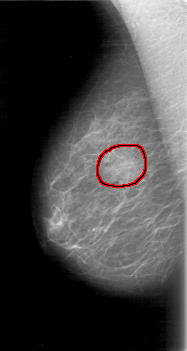

D_4015_1.RIGHT_MLO

RIGHT_MLO LINES 5251 PIXELS_PER_LINE 2791 BITS_PER_PIXEL 12 RESOLUTION 43.5 OVERLAY

FILE: D_4015_1.RIGHT_MLO.OVERLAY

TOTAL_ABNORMALITIES 1

ABNORMALITY 1

LESION_TYPE MASS SHAPE OVAL MARGINS OBSCURED

ASSESSMENT 0

SUBTLETY 4

PATHOLOGY BENIGN

TOTAL_OUTLINES 1

BOUNDARY